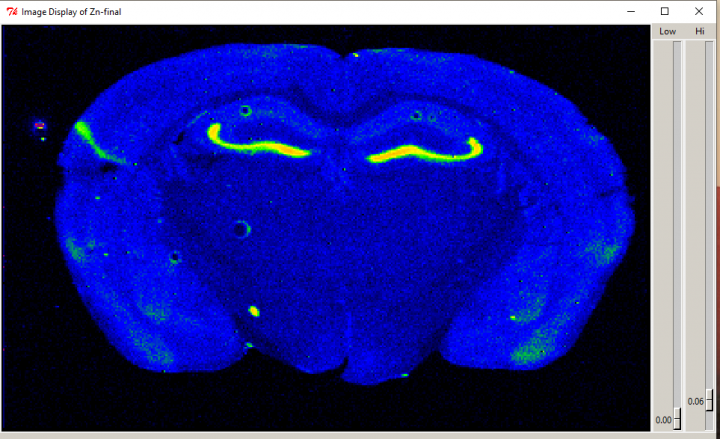

Graphic of a mouse brain with Alzheimer’s disease. Kelly Summers/ Supplied

Graphic of a mouse brain affected by Alzheimer’s disease. Kelly Summers/ Supplied